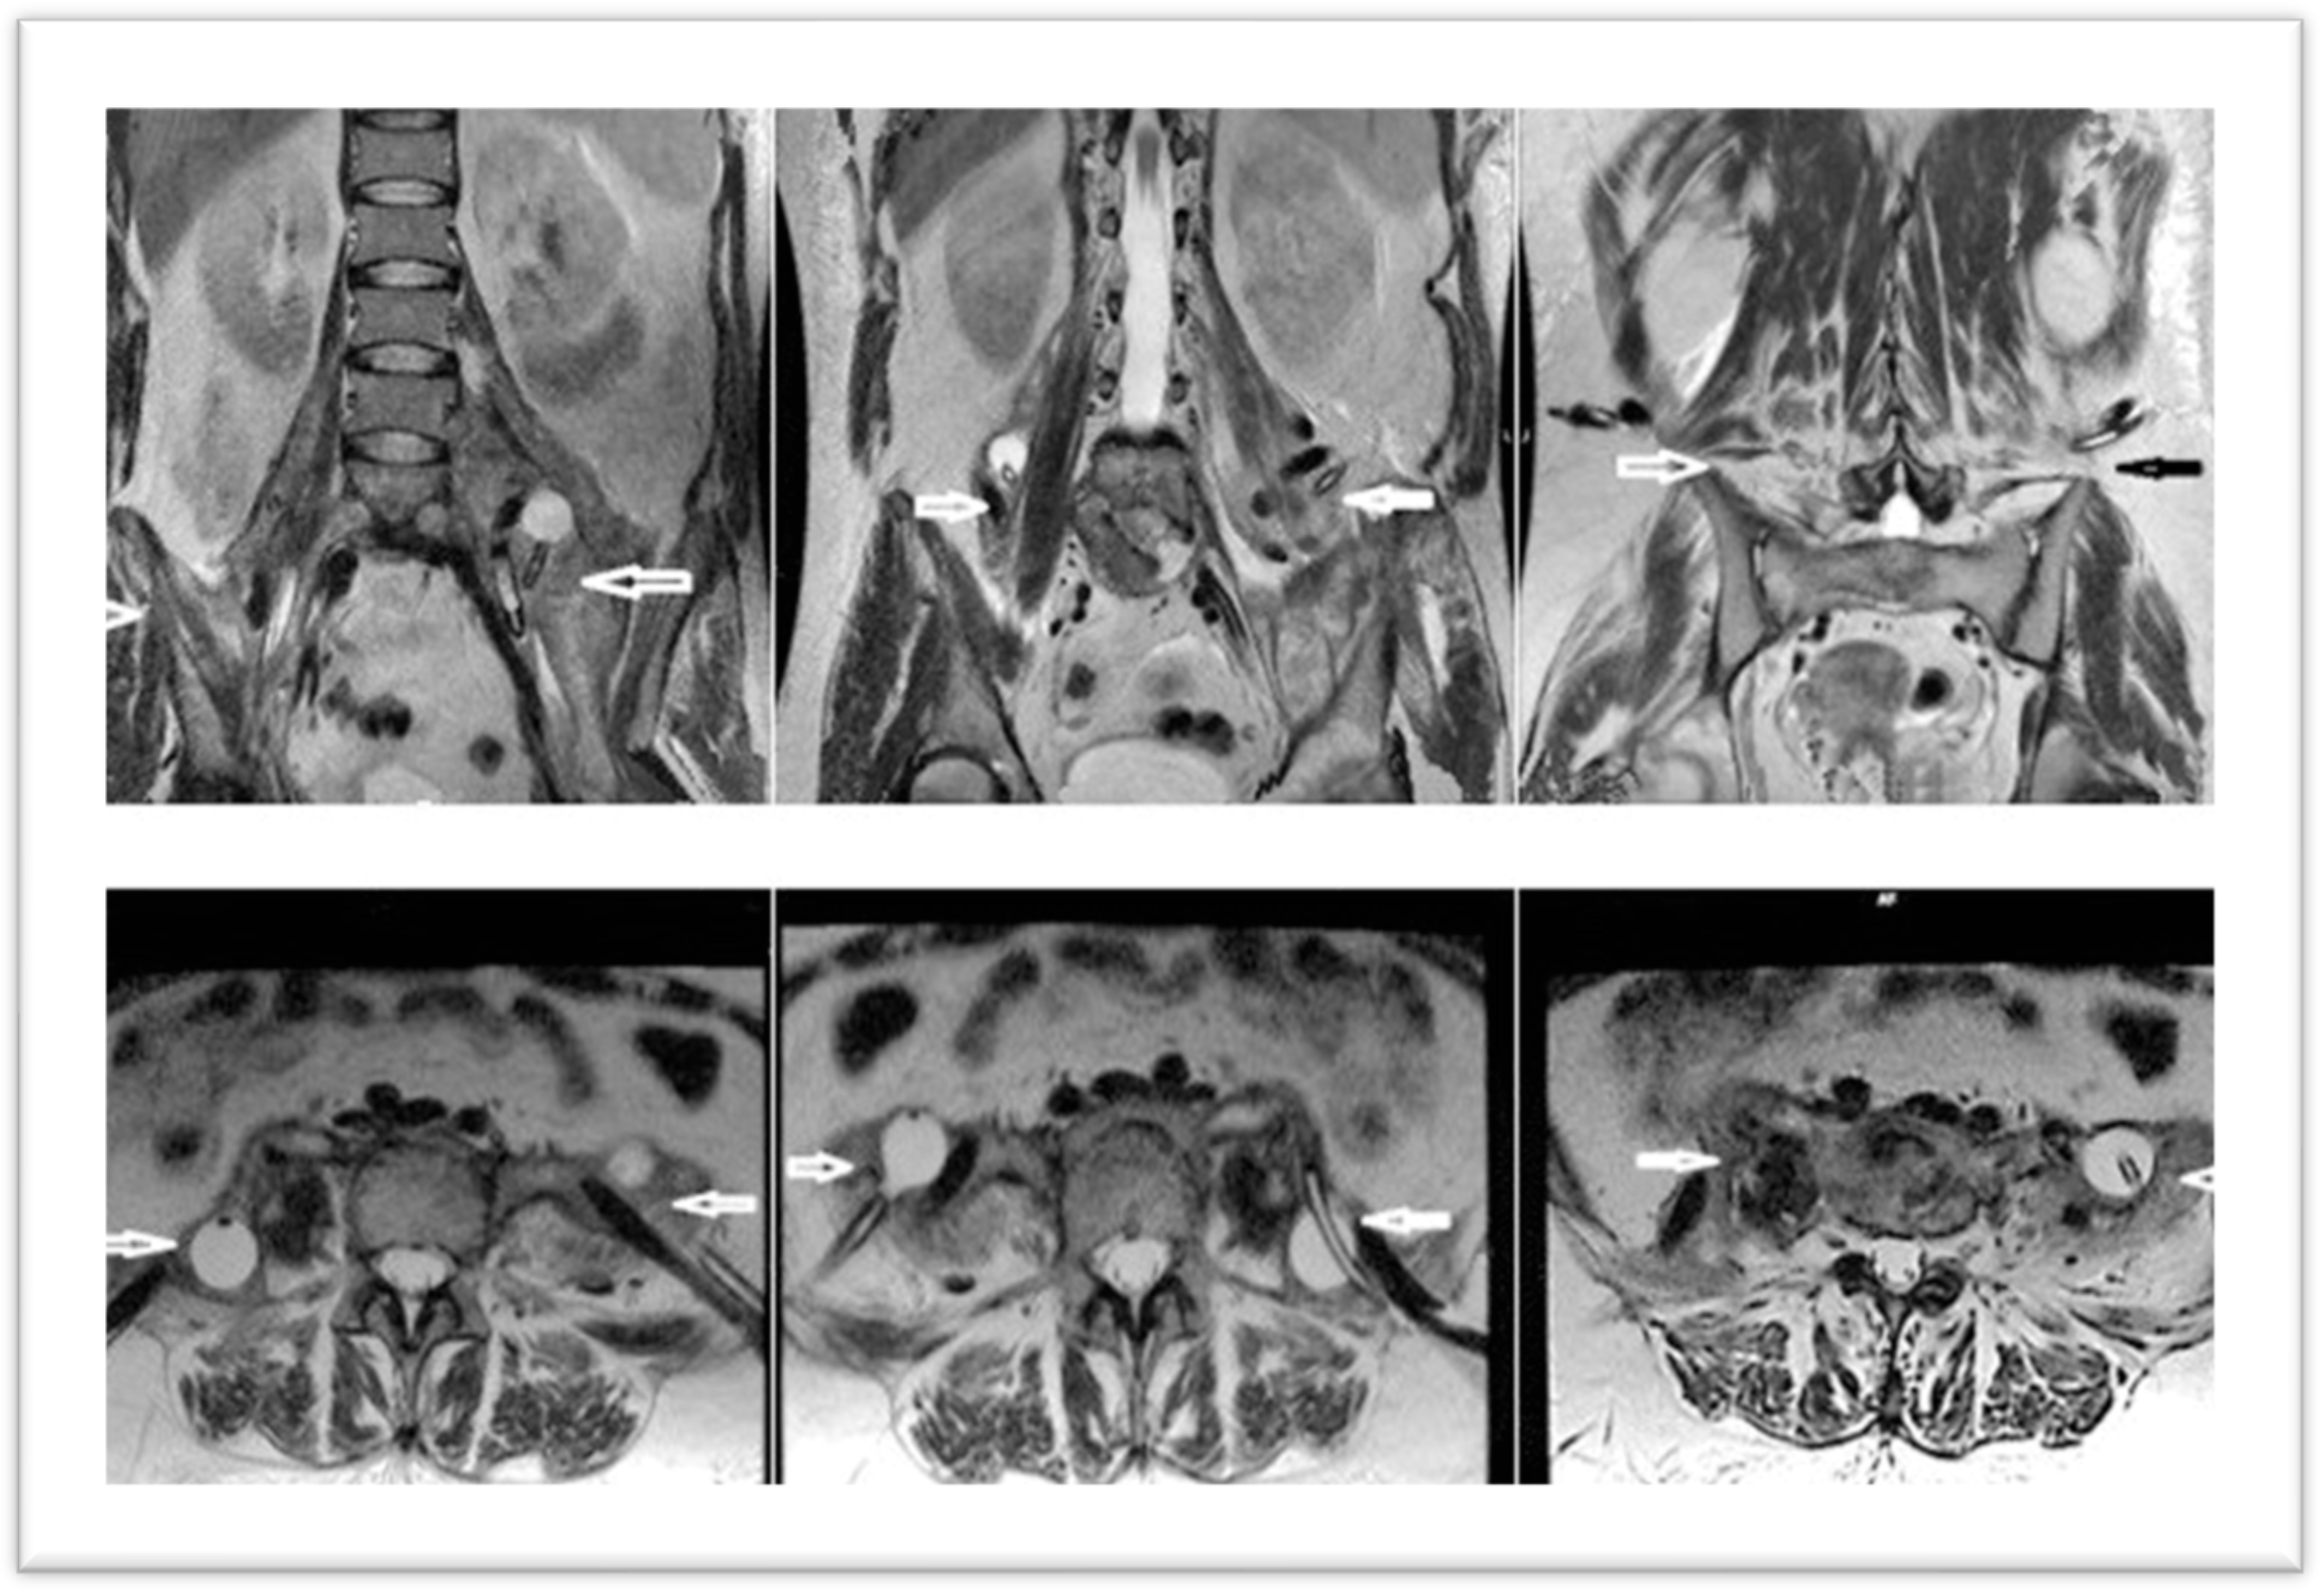

Two days postoperatively, a contrast-enhanced MRI revealed spondylodiscitis L4, L5, with L5 trans-somatic extension; small prevertebral collection; anterior epidural infection L4–S1; resolution of accumulations in the psoas major, regressive iliac abscess; and left coxofemoral osteoarthritis, characterized by pinching of the left coxofemoral joint space, with subchondral edema (Figure 5).

Figure 5. MRI aspect—two days postoperatively (arrows indicate resolution of abscesses under drainage).